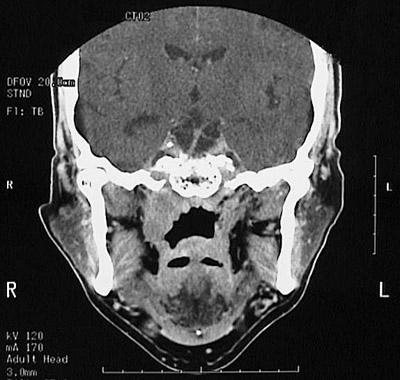

This head CT scan with contrast seen in axial view above demonstrates a 3 cm nasopharyngeal carcinoma on the right between the pterygoid plate anteriorly and the prevertebral and right carotid space posteriorly. In the coronal view below, this nasopharyngeal carcinoma is also seen.